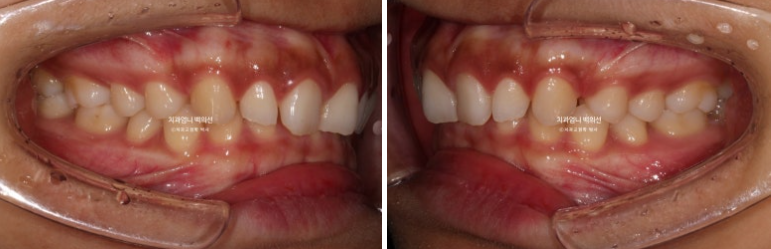

24.07

24년 7월까지, 첫 세트의 14개 장치를 모두 낀 후 모습입니다.

과개교합이 해소되며 아래앞니가 비로소 모습을 드러냅니다.

벌어진 틈을 깔끔하게 사라졌습니다.

삐뚤했던 앞니배열도 좋아졌습니다.

3.5개월의 변화라고 보기 힘들정도로 환자분은 열심히 껴주었고 치료계획도 완벽했습니다.